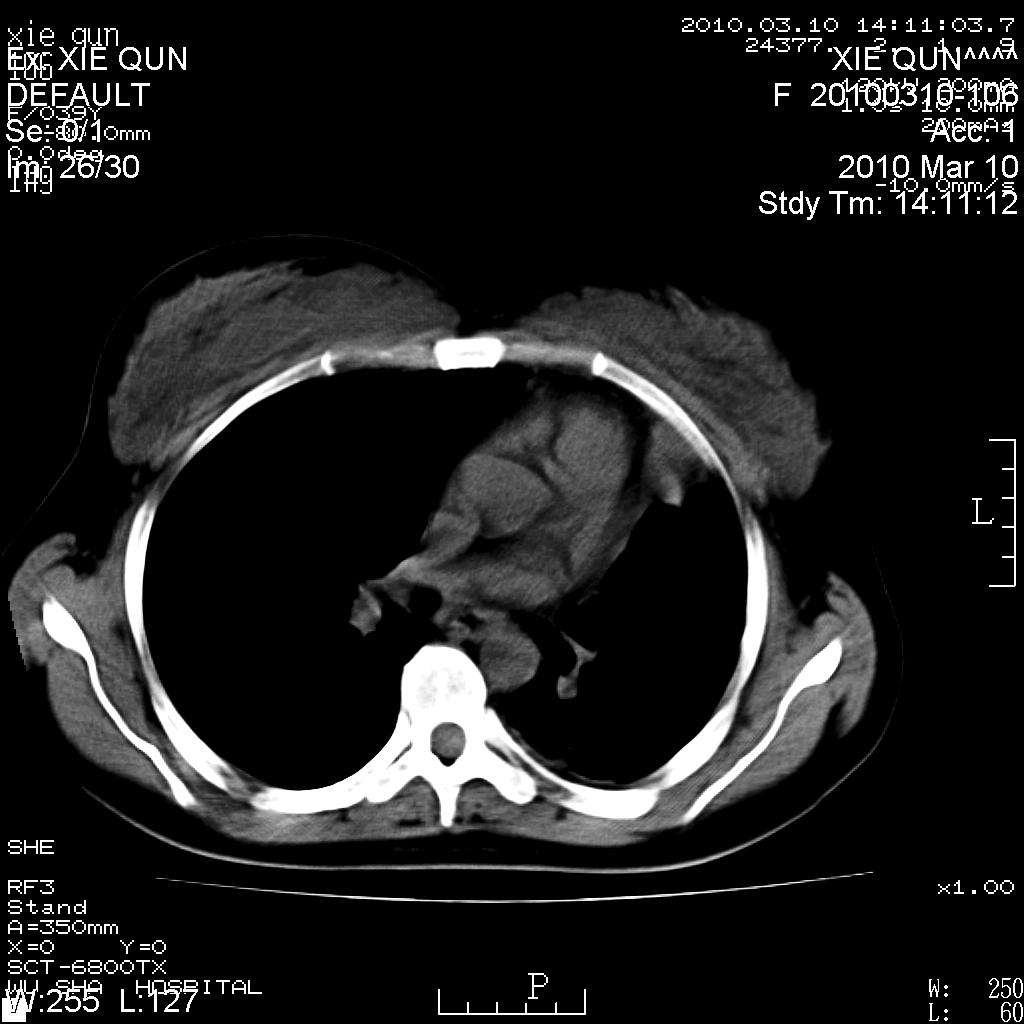

以下是引用心路寻觅在2010-3-24 17:28:00的发言:[br]两肺继发性tb左上肺空洞形成,建议痰检明确诊断。

以下是引用随光逐影在2010-3-24 19:19:00的发言:[br]两肺继发性结核并左上肺上叶空洞形成。